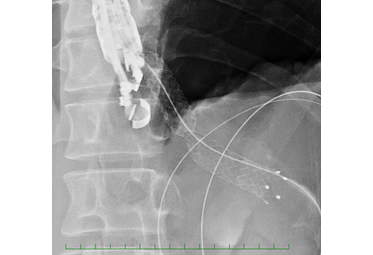

4) EUS- pancreatodrainage   (EUS-PD; 膵管ドレナージ)

• EUS-pancreatodrainageの画像1

• EUS-pancreatodrainagの画像2

• EUS-pancreatodrainageの画像3